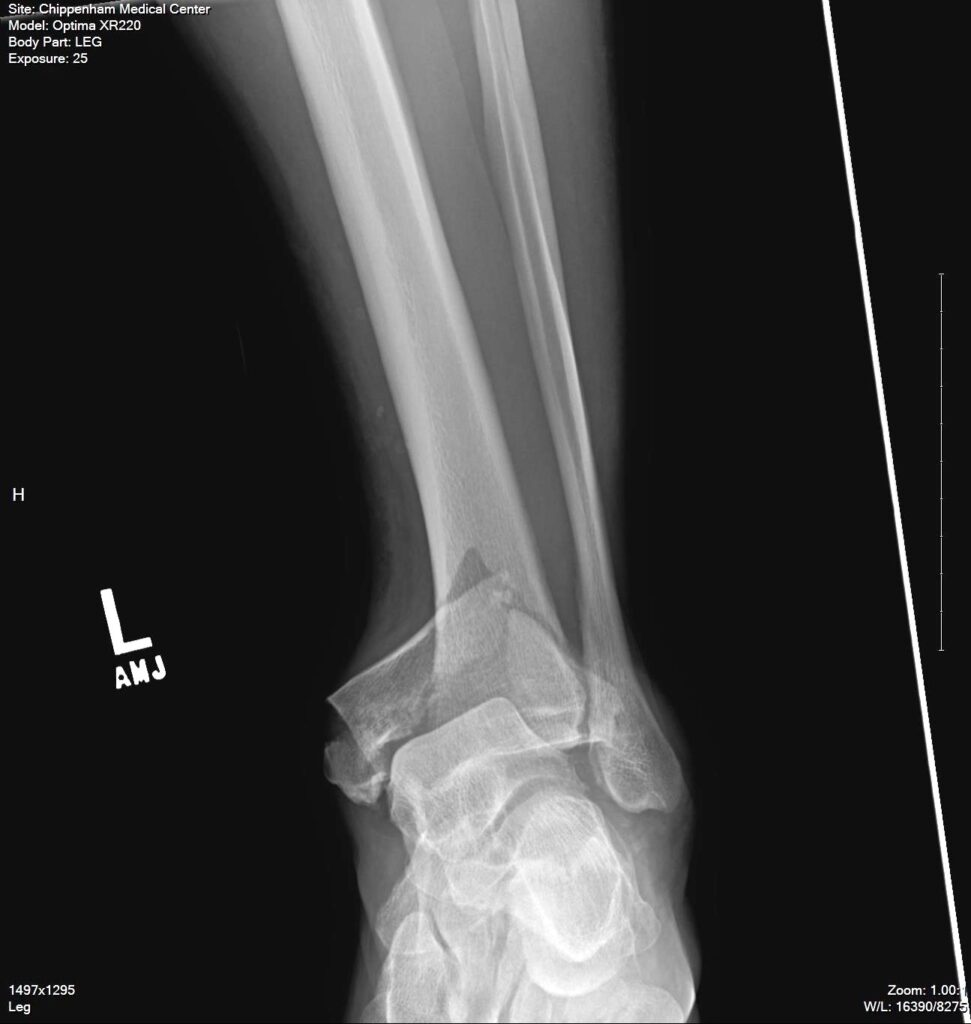

On August 28, 2017, Neal Fleenor took one step forward, and 20 vertical feet later, he was squatting on the ground looking up at the platform he had just dropped from. “I had been testing out a new lanyard on a zip line that failed on me when I stepped off the platform and the left ankle shattered on impact.” The impact shattered the bottom of his tibia. He also fractured his left first rib and got a L4 vertebrae compression fracture, but those were “relatively minor” compared to what happened to the ankle.